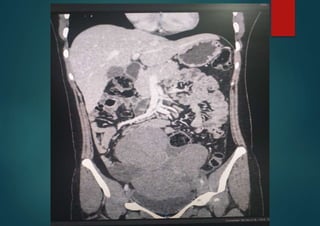

• #64 CT scan – Multilobulated solid masses with prominent fibrovascular septa. Post contrast imaging shows enhancement of the septae. Other- calcification may be present in a speckled pattern.